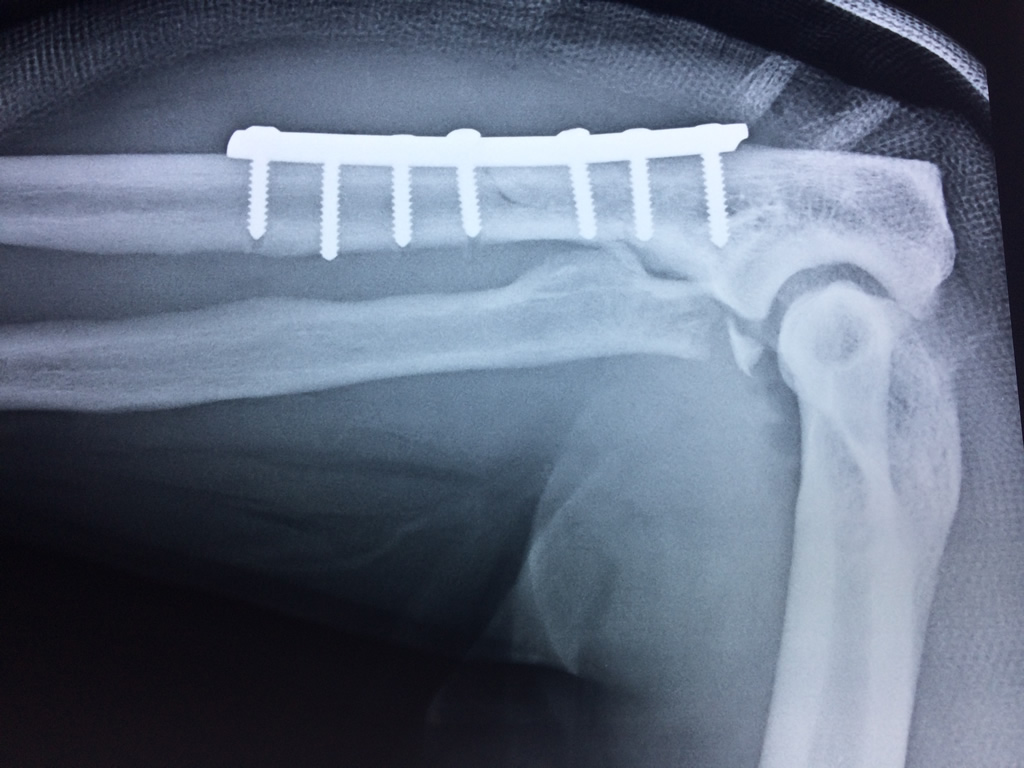

Cirugias en El Salvador - Codo